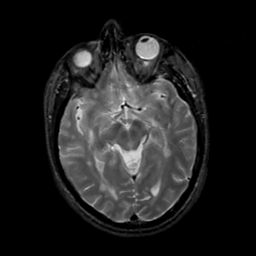

MR Study #5, March 10, 1991 -- Slice #23